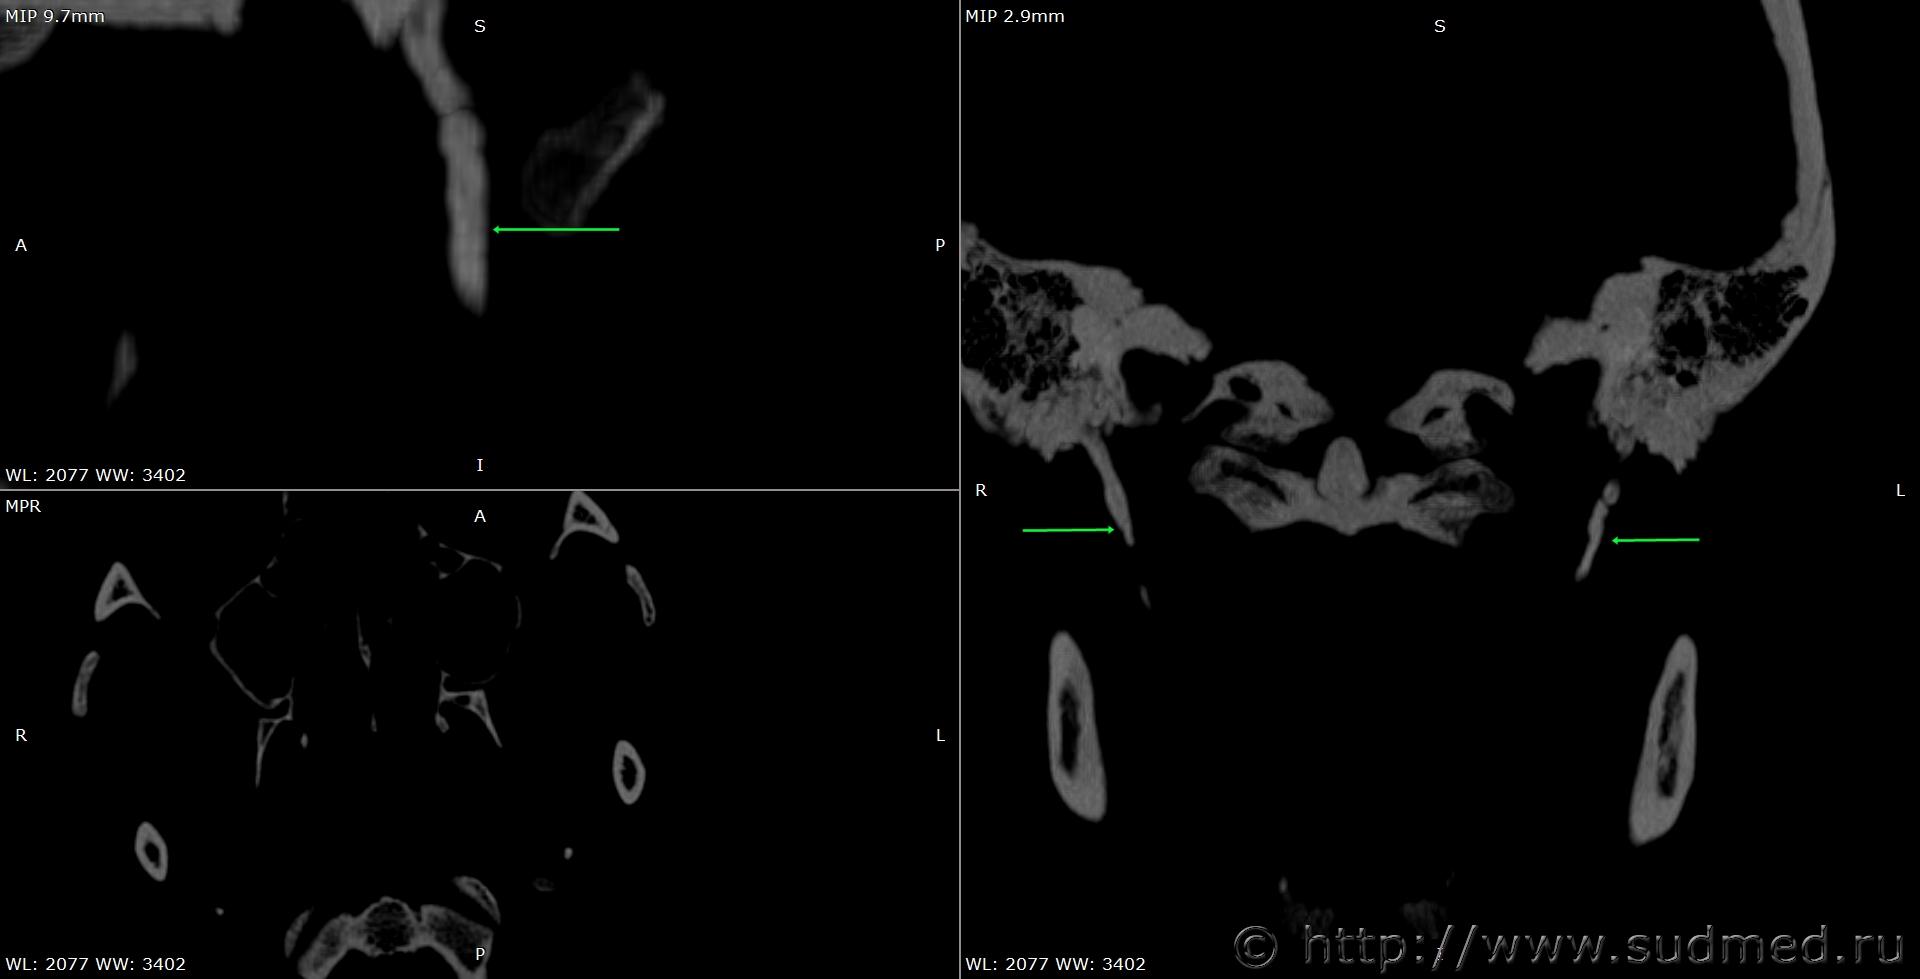

При экспертизе живого лица по медицинским документам встретились переломы шиловидных отростков височных костей. Женщина 39 лет, обратилась за медицинской помощью на 5-е сутки после травмы, тогда же провели РКТ. До этого никуда не обращалась. В протоколе РКТ отметили перелом шиловидного отростка левой височной кости, на снимках перелом на границе верхней и средней трети, дистальный отломок слегка смещен кпереди, каких-либо признаков заживления нет. Длина отростка 2,19 см. Судебная медицина - Прикрепленное изображение Также на КТ визуализируется перелом шиловидного отростка правой височной кости в нижней трети с выраженным смещением, думаю, отрывного характера (его длина 2,01 см), также без каких-либо признаков заживления Судебная медицина - Прикрепленное изображение; и гематома теменной области слева с переходом, в частности, на левую височную область, область левого сосцевидного отростка, левые околоушно-жевательную и скуловую области, левую боковую поверхность шеи Судебная медицина - Прикрепленное изображение, увеличение в объеме, нечеткость контура и разволокнение левой грудино-ключично-сосцевидной мышцы и левой ременной мышцы головы в верхней трети Судебная медицина - Прикрепленное изображение, вокруг них, в том числе кнутри от ременной мышцы, повышение плотности ПЖК Судебная медицина - Прикрепленное изображение; такие же изменения плюс повышение плотности левой подкожной мышцы шеи Судебная медицина - Прикрепленное изображение, увеличение в объеме и нечеткость контура левой околоушной слюнной железы, левая жевательная мышца не изменена Судебная медицина - Прикрепленное изображение. У подъязычной кости вижу нарушения целостности левого большого рога, но окостенение не завершено, края четко не визуализируются, поэтому о характере нарушений целостности не могу судить. Судебная медицина - Прикрепленное изображение Судебная медицина - Прикрепленное изображение В осмотрах врачей какие-либо изменения в области шеи, изменения голоса, соответствующие жалобы не отмечены; на 6-е сутки выставили острый фарингит. Помимо этой травмы есть переломы костей носа, там ничего особенного.

По срезам: шиловидные отростки какие-то тупоконечные. Подозрительна оссификация шило-подъязчных связок, что облегчает травирующему предмету возможность образовать перелом при воздействии на боковую область шеи.

Пересмотрела снимки, признаков оссификации связок нет.

Пересмотрела снимки после очередного раунда чтения литературы. Справа действительно больше похоже на оссификацию связки. Слева, скорее всего, тоже есть, перелом выше подозрительной области. Судебная медицина - Прикрепленное изображение Перелом справа снимаю. Большое спасибо за наводку!

Толщина срезов 1 мм, к слову.

Слева - похоже, что перелом, но назвать анатомическое образование я затрудняюсь, потому что не вижу четкой границы, где заканчивается шиловидный отросток (в кадре - длинный и тупой), а где начинается связка. Дифференцировать повреждения по механизму (удар - сдавление) тоже бы воздержался, а то после ознакомления с выводами пострадавшая возьмет и вспомнит, как ей там фиксировали, пока она сознание теряла.